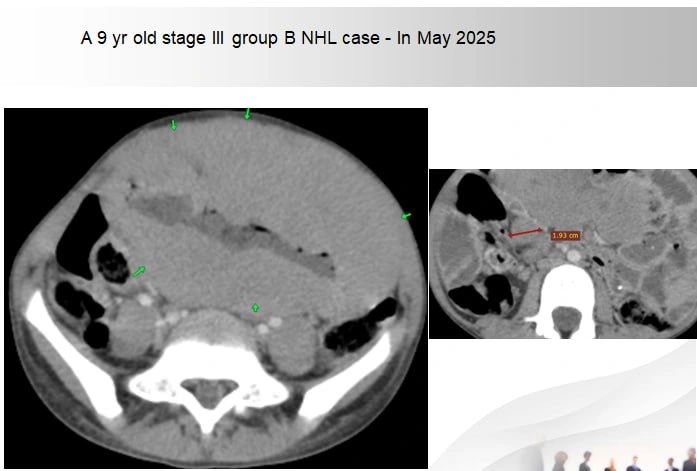

On examination, I found a large right lower quadrant mass extending toward the mid-pubis. A CT scan showed a thickened small bowel with large, homogeneously enhancing mesenteric lymph nodes. Under sedation, we performed a core-needle biopsy, bone marrow, and CSF examination.

The results confirmed Burkitt’s lymphoma (CD20 positive).